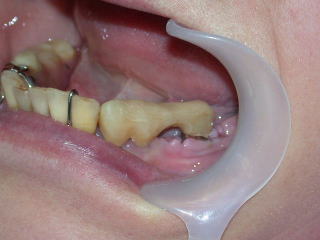

再び仮歯を付けてインプラントの固定を兼ねます。

平成20年3月、上部構造物4本を装着しました。

頬側面観です。

咬合面観です。

舌側面観です。

構造は白金加金製の金属フレームに、セラミックスを焼き付けてあります。

金属だけよりも審美性に優れ、セラミックスだけよりも耐久性は向上しますが、製作手順が複雑です。

歯科技工士の熟練した技術が必要となり、金額も高めです。

歯肉の状態は前回型取り時より平坦化して、炎症も治まりつつあります。